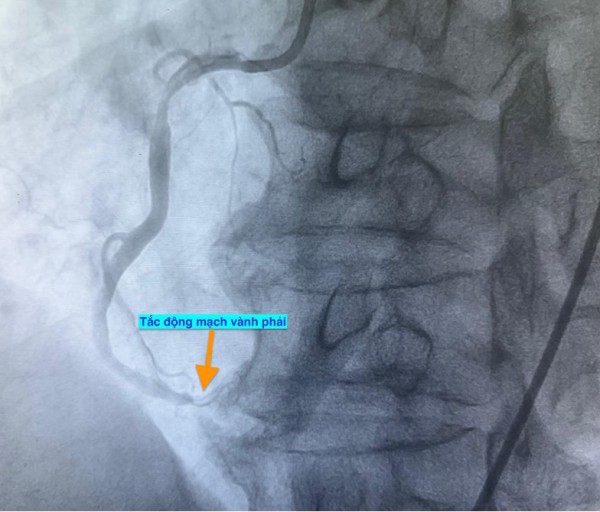

Trường hợp thứ ba, lúc 15 giờ 53 phút, nam bệnh nhân 78 tuổi nhập viện vì đau ngực. Bệnh nhân cho biết đau ngực từng cơn trong 3 ngày, ngày nhập viện thì đau ngực liên tục. Điện tim gợi ý nhồi máu cơ tim cấp; chụp mạch vành cấp cứu phát hiện bệnh nhân cũng tắc động mạch vành phải.

Hình ảnh chụp mạch vành cho thấy các bệnh nhân bị tắc mạch máu tim (do mảng xơ vữa, huyết khối) dẫn đến tình trạng thiếu máu cục bộ và nhồi máu cơ tim cấp